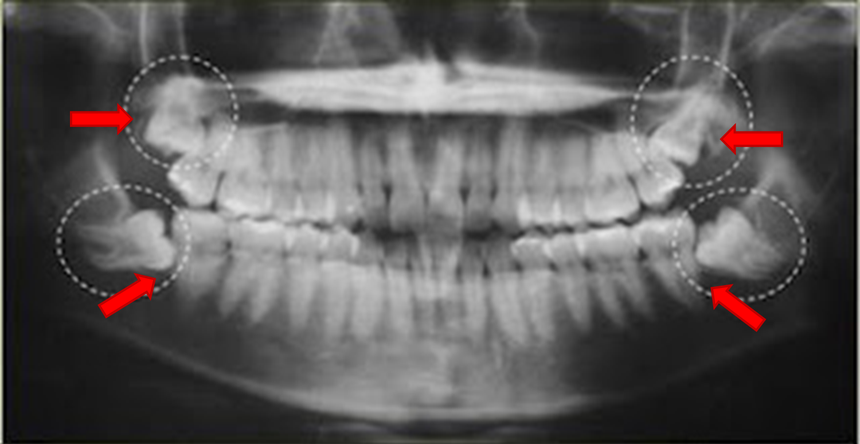

Designam-se por dentes do siso os 4 terceiros molares, localizados, à direita e à esquerda na parte posterior das estruturas dentárias.

Muitas das vezes, os maxilares não têm espaço suficiente para acomodar o surgir tardio dos dentes do siso, sendo essa uma das principais razões pelas quais “eles” causam mais problemas do que os outros dentes.

Estima-se que nove de cada dez pessoas apresenta, pelo menos, um dente do siso com problemas durante o nascimento desse dente.

Não deve existir controvérsia relativamente a esta questão. Não existe nenhuma justificação para a extração indiscriminada dos dentes do siso.

Os sisos que são saudáveis e normalmente posicionados não causam problemas.

Geralmente os dentes que permanecem inclusos, intra-ósseos, numa posição normal, é improvável que causem problemas.

Porém, se estes dentes estiverem numa posição anormal, o potencial para causar dano deverá ser devidamente avaliado por um médico dentista certificado.